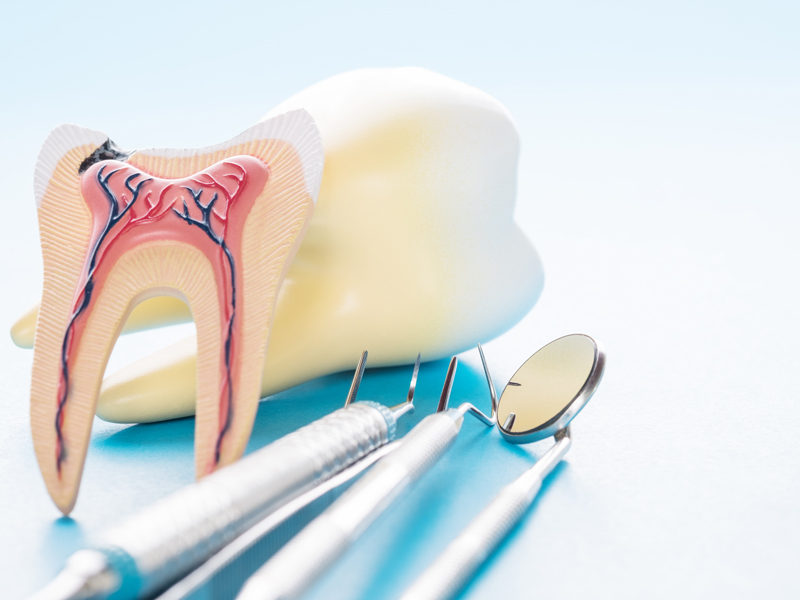

Im Inneren des Zahn befindet sich der Zahnnerv in einem Hohlraum. Er ist gut geschützt durch Zahnschmelz und Dentin. Der Zahnnerv besteht aus einem Mischgewebe aus Blutgefäßen, Nervenfasern und Bindegewebe. Sobald Bakterien in das Gewebe gelangen, kann sich der Zahnnerv irreversibel entzünden. Dies geschieht häufig durch Karies, die sich durch die harte Zahnsubstanz gefressen hat. Eine Wurzelkanalbehandlung schafft Abhilfe.

Bei der Wurzelkanalbehandlung wird das Gewebe des Zahnnervs aus dem Inneren des Zahnes entfernt und der Zahn mit einem Füllmaterial dicht verschlossen, um die Wiederbesiedlung mit Keimen zu verhindern. Der Zahnarzt legt die Wurzelkanäle frei, entfernt das Zahnnervgewebe, reinigt es und verschließt die Wurzelkanäle dann mit einem geeigneten Füllmaterial, um den darauf folgenden Verschluss durch eine Krone oder eine Füllung zu gewährleisten.